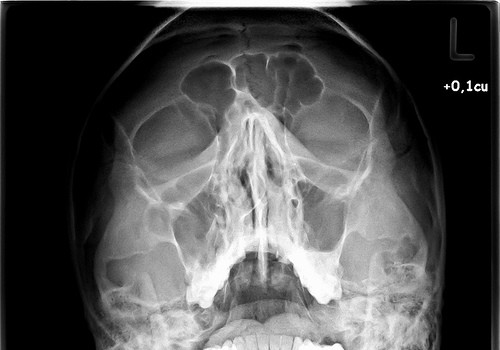

Skull Fractures

A skull fracture is a break in any of the eight cranial bones that enclose and protect the brain. Skull fractures usually but don't always result in injury to the brain. Skull fractures are not always easy to see. There may be bruising on the face, bleeding from the eyes, nose, or mouth, or swelling and tenderness around the impact area. Treatment of skull fractures is not always complicated, but always requires medical attention. Treat any suspicion of skull fracture as a medical emergency. Any time a bone breaks through the skin, of course, immediate medical treatment is essential to save life.